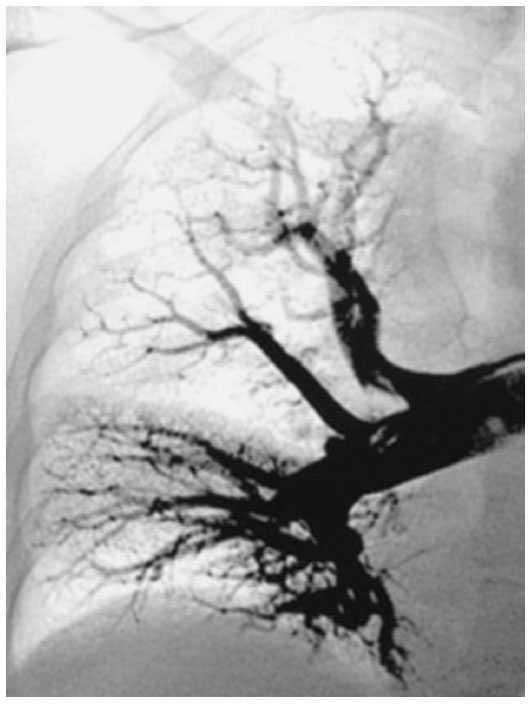

El pulmón es el órgano principal del aparato respiratorio. Consta de una estructura aérea, formada por el árbol bronquial y los alvéolos, y de una doble circulación, la bronquial y la pulmonar. Todo ello se encuentra bien delimitado en la cavidad torácica por las membranas pleurales y el diafragma. La vía aérea y la circulación se encuentran en íntimo contacto en los alvéolos, donde se realiza el intercambio de gases a través de la membrana alvéolo-capilar, a fin de que el pulmón pueda conseguir realizar una de sus principales funciones, que es aportar oxígeno a la sangre y eliminar CO2 (fig. 1)4.

Figura 1. Representación gráfica de la anatomofisiología del pulmón que muestra la íntima relación entre el árbol bronquial y la circulación pulmonar.

El árbol bronquial está constituido por los bronquios, unos conductos tubulares en que se bifurca la tráquea, y que presentan unas ramificaciones progresivas arboriformes, de diámetro decreciente hasta los bronquiolos terminales, en donde se encuentran los alvéolos pulmonares, divertículos terminales del árbol bronquial en los que tiene lugar el intercambio gaseoso.